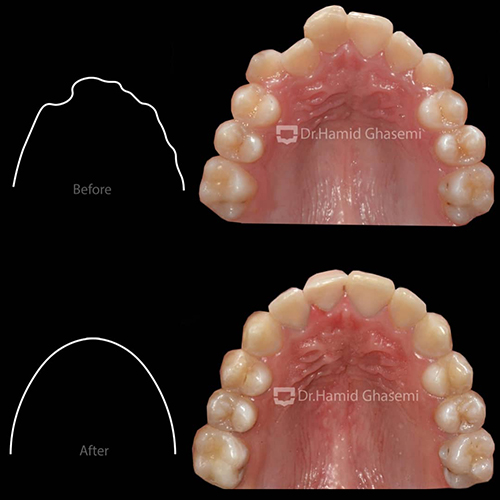

- کمبود فضا در فک بالا جهت رویش دندانها

در مرحله اول، با استفاده از اکسپاندر و پیچهای داخل کامی جهت شل شدن درز بین فکی در فک بالا و سپس اعمال نیروی خارج دهانی فیس ماسک جهت جابهجایی فک بالا به سمت جلو انجام شد.

در مرحله دوم، درمان ارتودنسی ثابت با استفاده از براکتهای دیمون استفاده شد. انتخاب براکتهای دیمون جهت عریض کردن قوس فکی و دندانی انجام شد که تأثیرات آن بر عریض شدن لبخند بیمار بسیار مشهود است.

- عریض شدن فک بالا